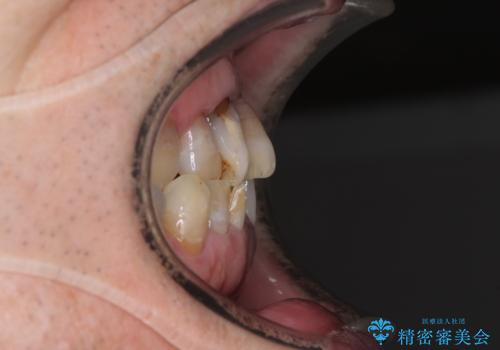

- 前歯の叢生と臼歯のクロスバイトを気にして来院された患者様です。

急速拡大装置による上顎の側方拡大を行い、その後はインビザラインより歯列を改善することとしました。

20代後半以降の男性は上顎骨の側方拡大処置の成功率が低く、今回も骨を拡大することができませんでした。

しかしながら、歯列を側方に拡大することができ、その後はインビザラインにて叢生を解消することができました。